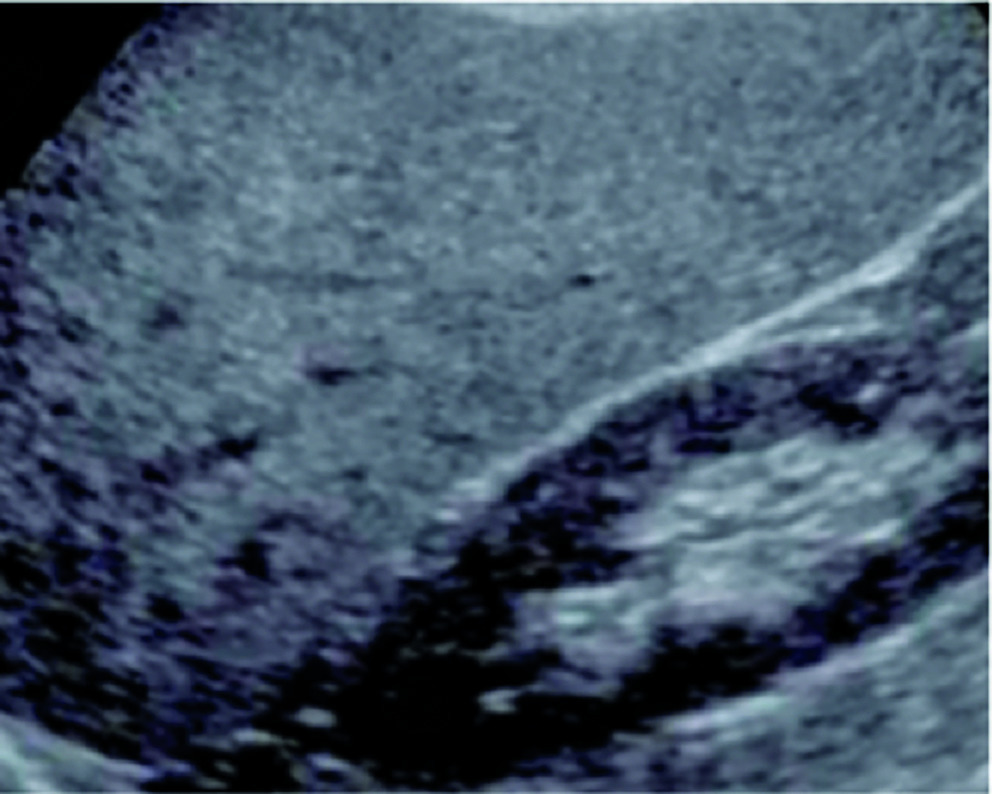

– échographie abdominale : aspect hyperéchogène (quand au moins 30 % des hépatocytes sont stéatosiques). Sa sensibilité est de 80 % et sa spécificité est supérieure à 90 % (pas de supériorité du scanner) ;